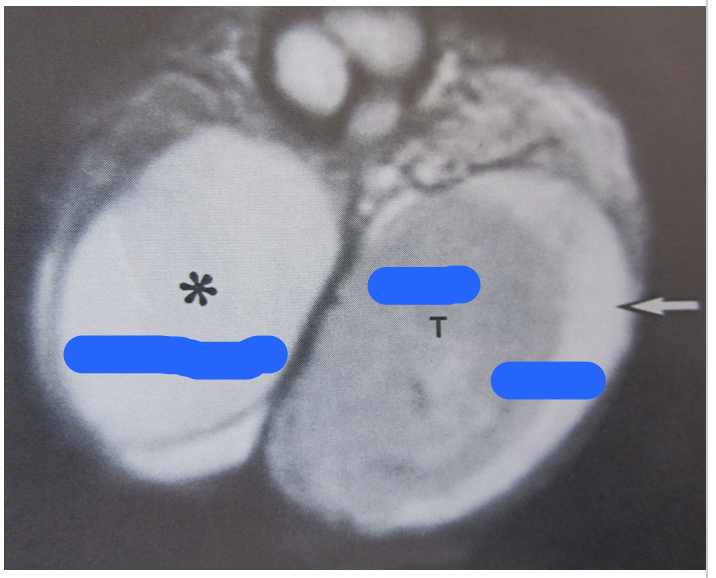

What do the letters represent?

SV: seminal vesicles

P: Prostate

U: Urethra